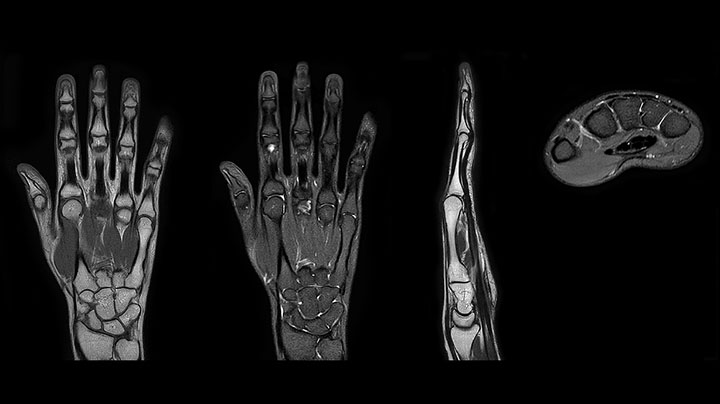

Clinical cases from Radiology Schiffer

MRI of hand and wrist with large FOV

Prodiva imaging of the hand covers the fingertips and includes the full wrist as well. The dS MSK M coil is easy to use.